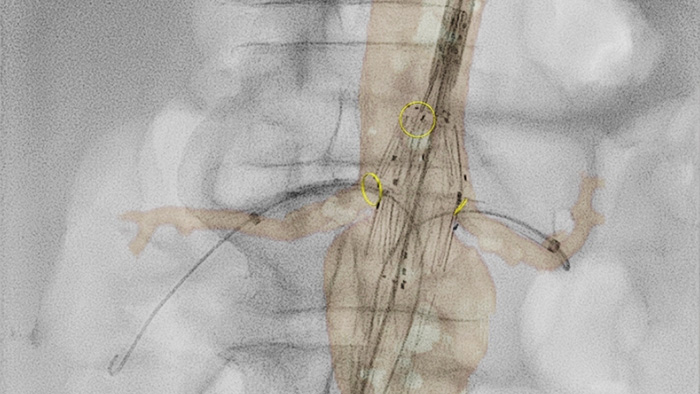

VesselNavigator : reducir la necesidad de contraste

VesselNavigator proporciona una hoja de ruta 3D, intuitiva y continua, basada en conjuntos de datos de la angiografía por tomografía computarizada (ATC) y la angiografía por resonancia magnética (ARM) existentes para guiarlo a través de la vasculatura durante los procedimientos aórticos. En un estudio se demostró un promedio de 170 ml de reducción del contraste durante la reparación endovascular de aneurismas aórticos complejos con el uso de la guía de fusión de imágenes de la ATC de VesselNavigator.1 En otro estudio se mostró una reducción en el tiempo promedio del procedimiento de 6,3 a 5,2 (1,1) horas durante la FEVAR/BEVAR con la guía de fusión de imágenes de la ATC de VesselNavigator.2